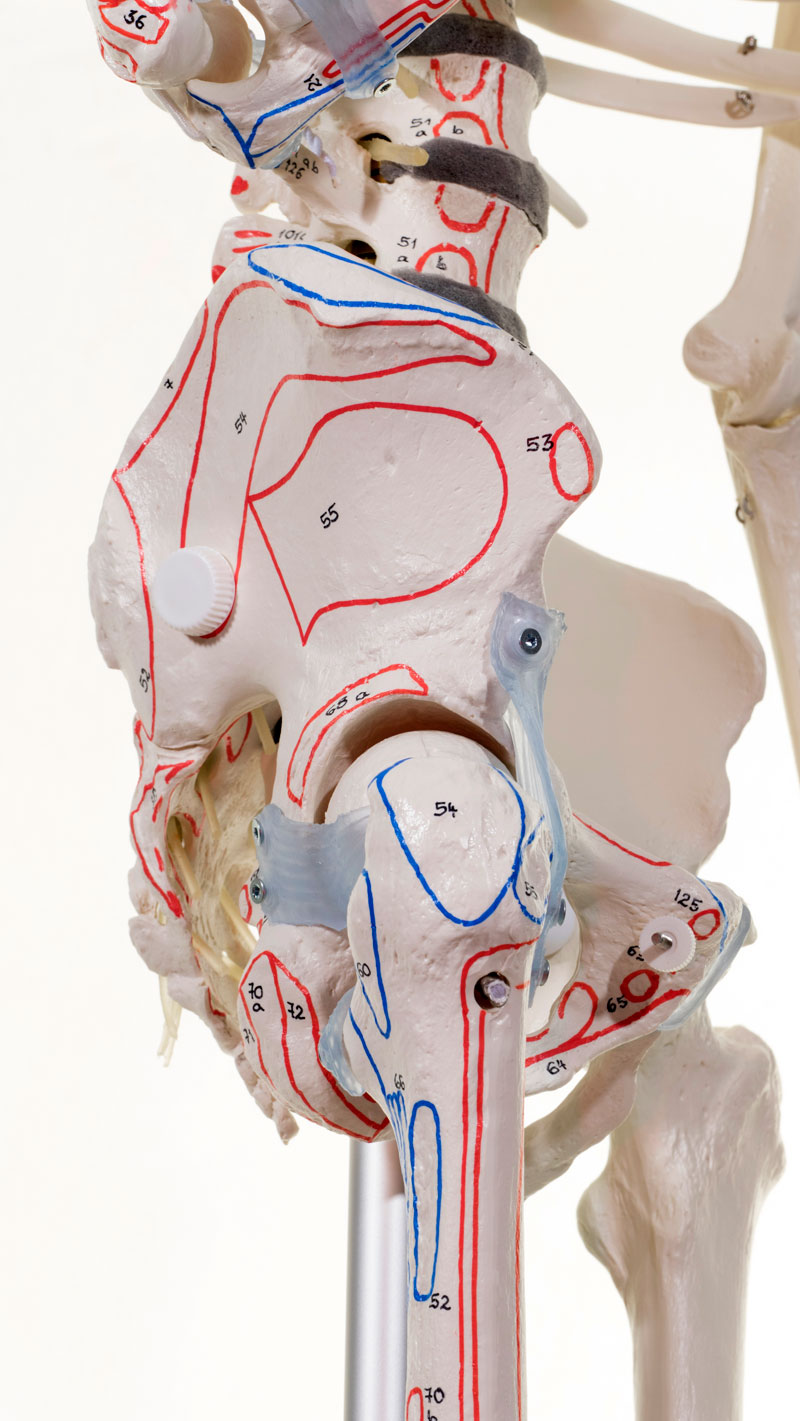

Ligaments

Avec ligaments